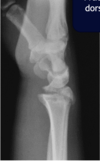

Fratura do platô tibial lateral - Schatzker tipo 2 (traço de fratura + depressão do plato lateral).